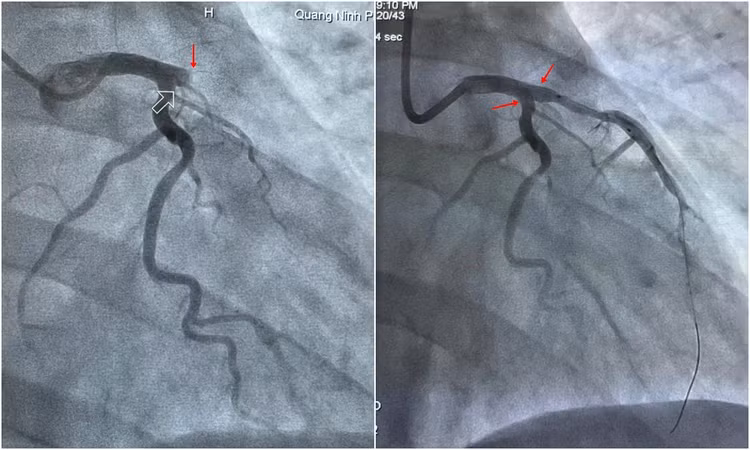

Hội chẩn khoa đánh giá bệnh nhân trong tình trạng nguy cấp, tiên lượng nặng, nguy cơ diễn biến cao. Kíp can thiệp ngay lập tức được huy động và nhanh chóng chuyển bệnh nhân lên phòng can thiệp. Kết quả chụp mạch vành qua da cho thấy tắc hoàn toàn động mạch liên thất trước ngay từ đoạn đầu, đồng thời hẹp 50% các nhánh mạch khác. Chỉ định can thiệp đặt stent tái thông động mạch, tưới máu lại cho cơ tim ngay lập tức được đặt ra.

| Hình ảnh mạch vành bị tắc hoàn toàn được đặt stent tái thông thành công. |